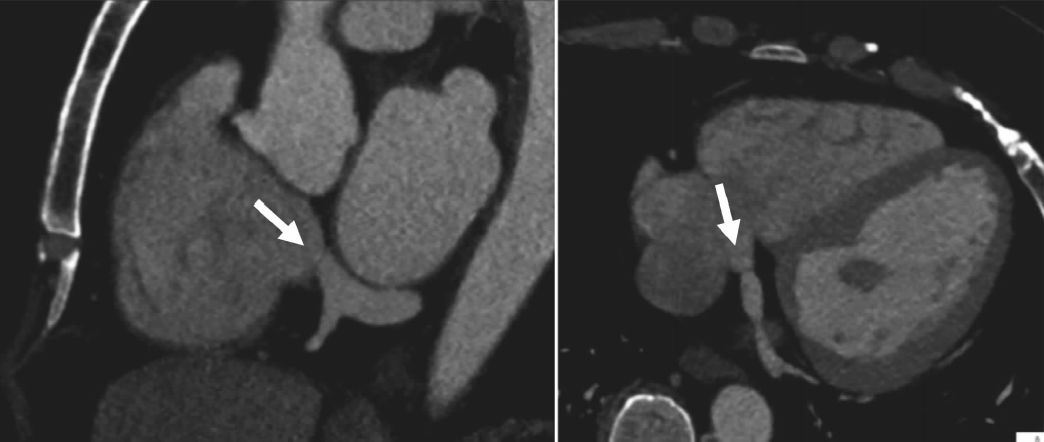

7 冠状窦瓣.图中可见位于冠状窦口的薄瓣膜(箭头).